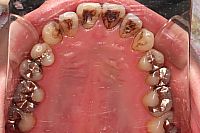

PMTC前

PMTC後